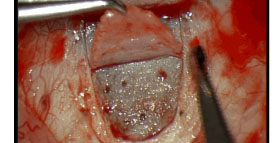

Sclerectomia profonda